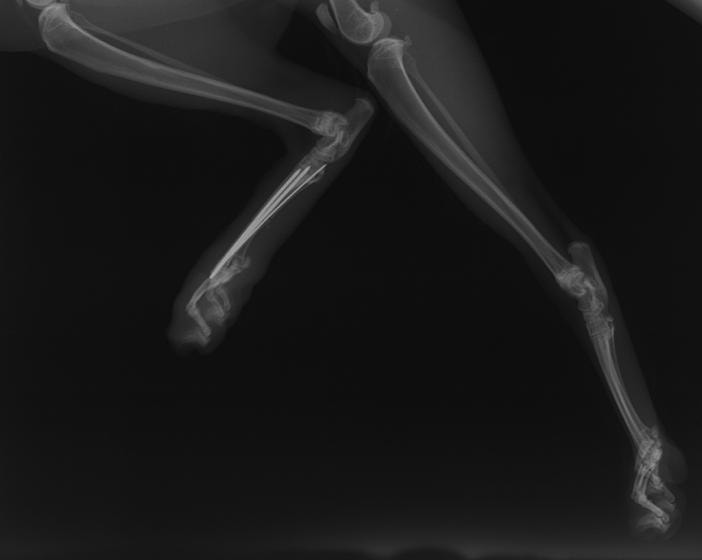

症例3:キルシュナーワイヤーのピンニングによる整復

ペルシャ猫 11ヶ月齢 雄

他院にて左大腿骨遠位の成長板骨折(salter-harrisⅠ型)が認められており、治療相談を目的として来院。当院にて、キルシュナーワイヤーを用いたピンニングにより骨折部位の整復を行いました。術後の経過は良好で、現在も経過観察中です。

術前レントゲン

術後レントゲン

機器

Arthrex社のターゲティングデバイスを用いてピンニングの位置を調整することで、確実な固定を行っています。当院ではこの手術器具以外にも、人の手術にも使用される様々な器具を導入し、手術精度を高め、また医療メーカーと新しい器具の開発、試作にも取り組んでおります。